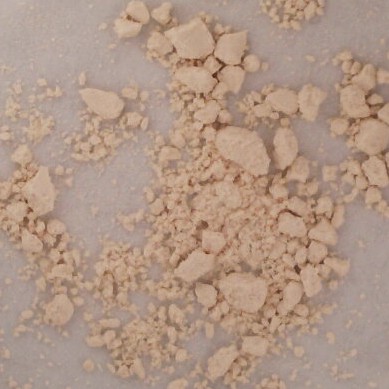

Fentanyl: NegativeBenzodiazepine: NegativeNotes: Imprint: DD/8. This sample is mostly pill fillers/binders with a small quantity of hydromorphone.Vancouver, BC 01/18/2025 Category: OpioidDescription: White GranulesSold as: DownResult: Para-Fluorofentanyl Base Desalkylgidazepam Caffeine Uncertain Match

Fentanyl: PositiveBenzodiazepine: PositiveNotes: Vancouver, BC 01/18/2025 Category: OtherDescription: White GranulesSold as: FasoracetamResult: Fentanyl: NegativeBenzodiazepine: NegativeNotes: Vancouver, BC 01/18/2025 Category: StimulantDescription: Colourless CrystalSold as: MethamphetamineResult: Fentanyl: NegativeNotes: Vancouver, BC 01/18/2025 Category: OpioidDescription: Green PebbleSold as: DownResult: Fentanyl: PositiveBenzodiazepine: NegativeNotes: Vancouver, BC 01/18/2025 Category: OtherDescription: White PowderSold as: PhenylpiracetamResult: Fentanyl: NegativeBenzodiazepine: NegativeNotes: This sample did not resemble our reference for phenylpiracetamVancouver, BC 01/18/2025 Category: StimulantDescription: White PebbleSold as: CocaineResult: Fentanyl: NegativeNotes: Vancouver, BC 01/18/2025 Category: PsychedelicDescription: Colourless CrystalCode: golden dogSold as: MDMAResult: Fentanyl: NegativeNotes: Vancouver, BC 01/18/2025 Category: StimulantDescription: Colourless CrystalSold as: MethamphetamineResult: Fentanyl: NegativeNotes: Vancouver, BC 01/18/2025 Category: StimulantDescription: White PowderSold as: CocaineResult: Fentanyl: NegativeNotes: The uncertain was too small to confirm; however, it shares similarities to multiple minerals and carbohydrates.Vancouver, BC 01/18/2025 Category: StimulantDescription: White ChunkSold as: Cocaine BaseResult: Fentanyl: NegativeNotes: Vancouver, BC 01/18/2025 Category: PsychedelicDescription: Light Blue PowderSold as: MDMAResult: Fentanyl: NegativeNotes: Vancouver, BC 01/18/2025 Category: StimulantDescription: White ChunkSold as: Cocaine BaseResult: Fentanyl: NegativeNotes: Vancouver, BC 01/18/2025 Category: UnknownDescription: Brown ChunkSold as: UnknownResult: Opium Uncertain Carbohydrate